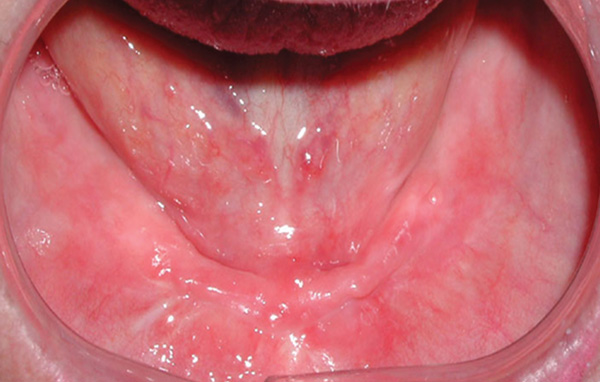

The mandibular arch has its own unique issues. Unlike the maxillary arch, the palatal vault is not a problem, but it is necessary to manage the floor of the mouth with regard to its depth. As resorption in the mandible progresses, the vestibule and floor of the mouth become shallower. Muscles related to the tongue exert lifting forces on the removable prosthesis’ lingual flange, which becomes more significant as resorption progresses. As with the maxillary arch, as the available ridge height above the depth of the vestibule shortens, less ridge is available to provide lateral bracing to the prosthesis during function (Figure 8).

Examination of the residual ridge at the treatment-planning phase can assist in identification of any anatomic obstacles that will require use of a bar (or recommendation of a fixed approach) or when freestanding implants with attachments can be used. An anatomic landmark to keep in mind when evaluating the patient is the genial tubercles. As ridge height is lost in the anterior, the ridge crest migrates toward the genial tubercles, which results in a shallower floor of the mouth and more lifting of the prosthesis from the muscles located in this area of the mouth (Figure 9). When it is noted that the genial tubercles are positioned at or superior to the crest of the ridge, this signifies severe bone resorption. Utilization of freestanding implants is precluded, as the ridge offers no lateral bracing, and thus stability of the prosthesis is compromised (Figure 10). The same test that was recommended in the maxillary arch to test lateral stability of the current denture can be performed in the mandibular arch. This also helps illustrate to the patient why freestanding attachments are not ideally suited for the situation and why a bar would be recommended. Discovering these issues during the treatment-planning phase is better than later when the prosthetics is being fabricated and inserted.

Fig 9. Mandibular arch with shallow vestibular and floor-of-the-mouth depth.

Figure 9